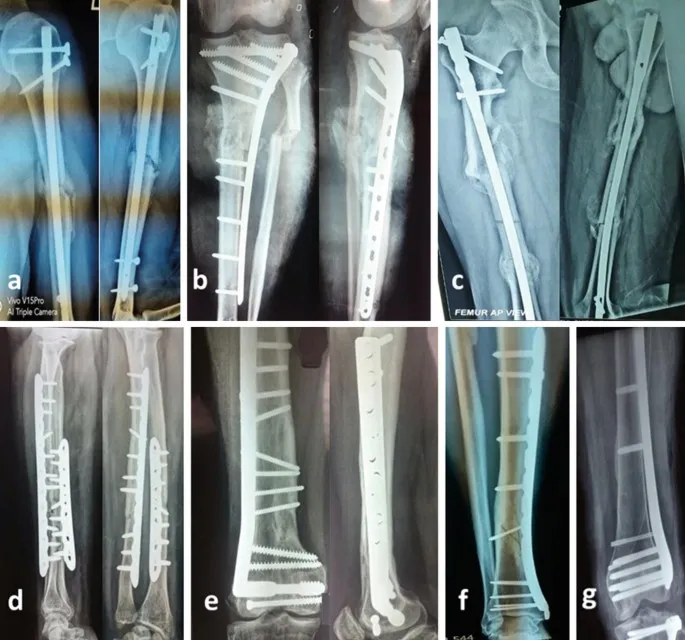

Implant Types - Hardware Heroes

| Locking (LCP) | Angular stability (internal fixator), for poor bone quality | Other Implants: |

- K-wires: 0.6-3.0mm; fixation, guides.

- IM Nails: Load-sharing; long bone diaphyseal #.

- Cerclage Wires: Encircle fragments.